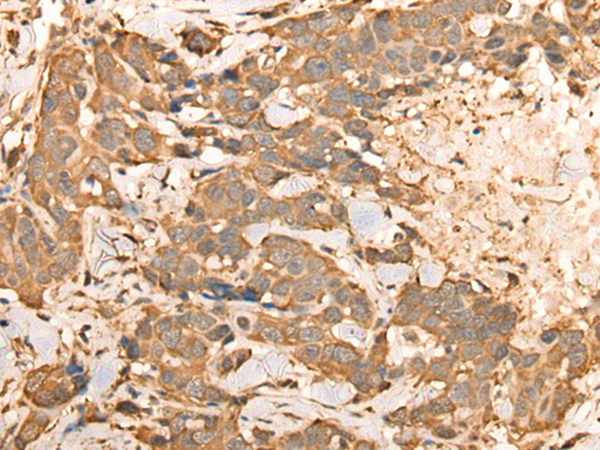

IHC positive control:

Human esophagus cancer and human thyroid cancer

IHC Recommend dilution:

25-100